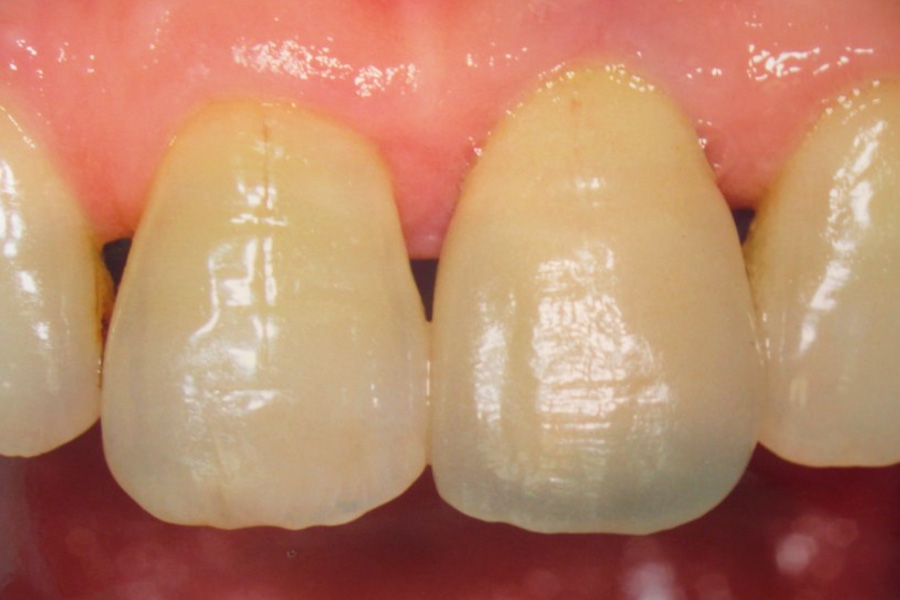

天然歯に馴染む前歯にしたい

- 天然歯に馴染む前歯にしたい

- 上顎前歯インプラント治療(e-max)

- 歯髄壊死、歯根吸収、歯肉退縮、ブラックトライアングル